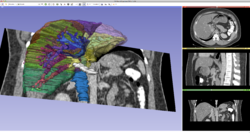

Slicer4 3D Visualization of DICOM images for Radiology Applications

- The 3D Visualization of DICOM images for Radiology Applications course guides through 3D data loading and visualization of DICOM images for Radiology Applications in Slicer4.5.

- Author: Sonia Pujol, Ph.D., Kitt Shaffer, M.D., Ph.D., Ron Kikinis, M.D.

- Audience: Radiologists and users of Slicer who need a more comprehensive overview over Slicer4 visualization capabilities.

- Modules: DICOM, Volumes, Volume Rendering, Models.

- Based on: 3D Slicer version 4.5

- The 3DVisualizationDICOM_part1 and 3DVisualizationDICOM_part2 datasets contain a series of MR and CT scans, and 3D models of the brain, lung and liver.